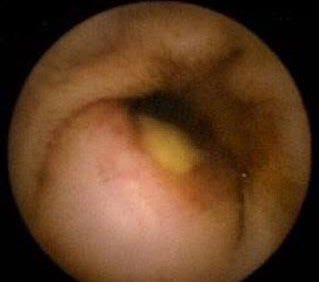

1️⃣ Lymphocytic or Granular Duodenitis

📍 Seen in: Sjögren syndrome

🔎 Chronic diarrhea, malabsorption

🔬 Biopsy: intraepithelial lymphocytosis

❗️May mimic celiac but with negative TTG/EMA Image